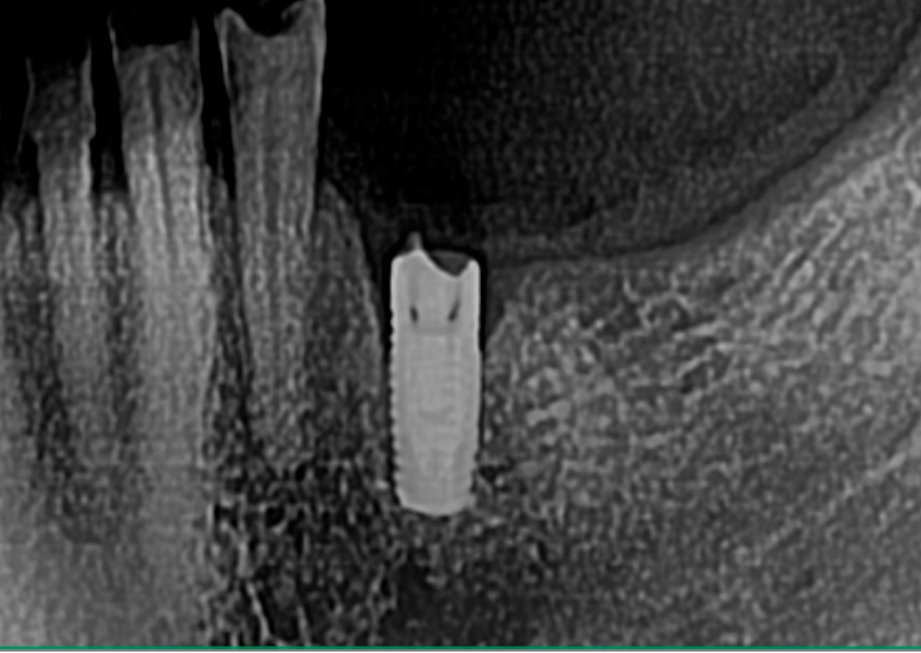

Buenas tardes! Paciente que viene con corona floja, era cementada y um compañero intentando apretar el tornillo del pilar ( que se había aflojado) fresó la cabeza del tornillo. Necesito [...]